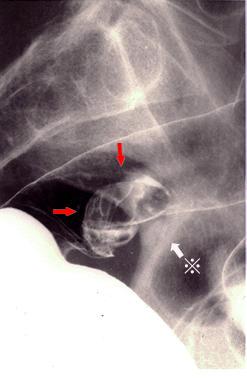

난소의 기형종이 직장의 점막면을 압박하여、천파한 대장의 종양양 병변

종양양 병변/근접장기로부터의 침윤

대장/직장

X-P

30~34